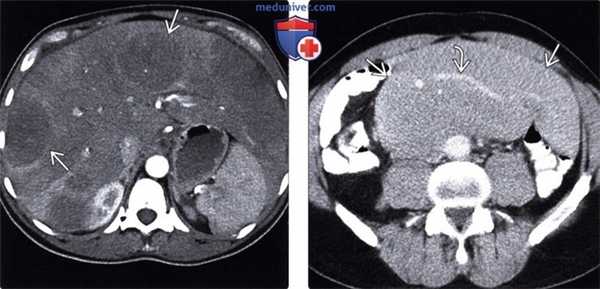

(Слева) ПЭТ/КТ, аксиальная проекция, этот же пациент: ФДГ-положительная лимфаденопатия при НХЛ.

(Справа) МРТ, Т2-ВИ, SS FSE, аксиальная проекция: у этого же пациента выявлено парааортальное образование , имеющее ИС от высокой до умеренной.